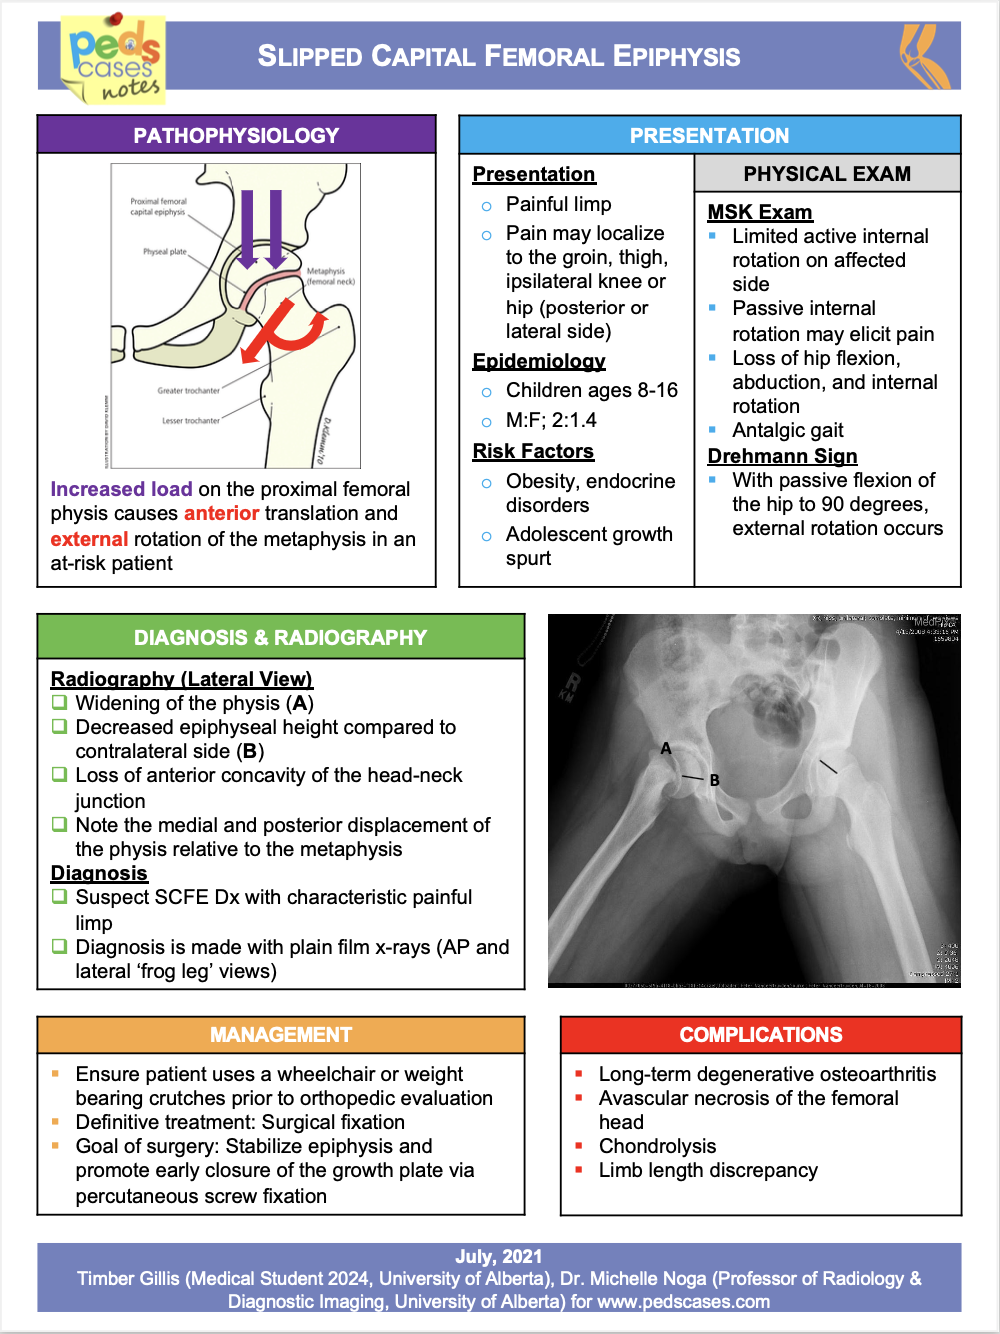

Slipped Capital Femoral Epiphysis | PedsCases

www.pedscases.com

www.pedscases.com